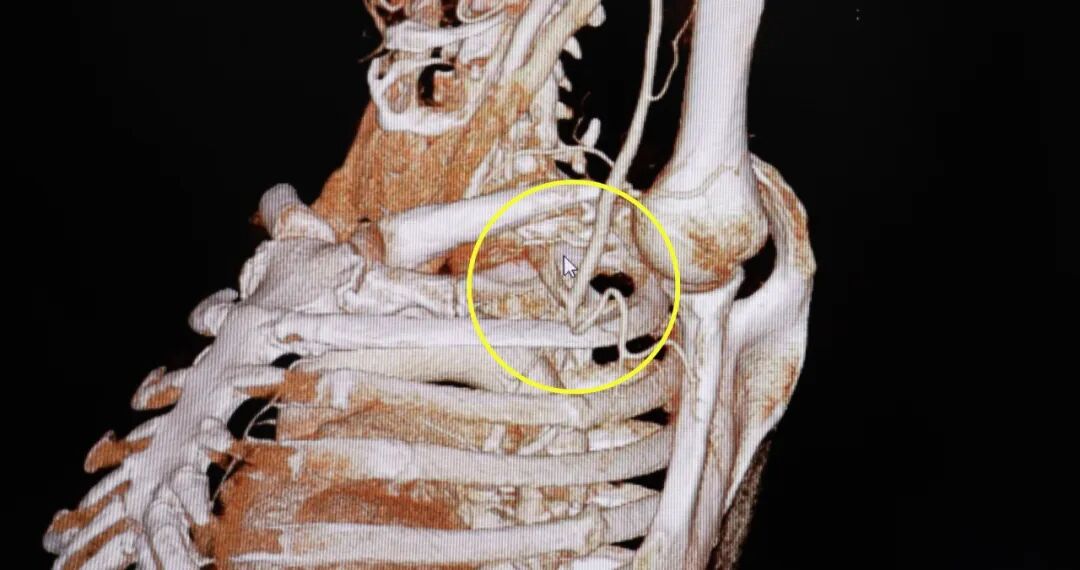

住院后,西安高新医院骨科一病区杨鹏主任为张大爷做了全面检查,发现他的情况比想象中复杂多了,他左边腋下和锁骨下面的大静脉里,已经形成了血栓(就是血管里的血凝固成了硬块),左前臂内侧还有个血肿。